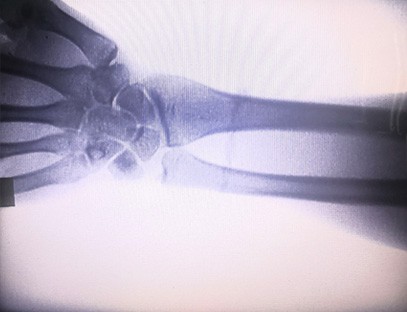

ایک پورٹیبل ایکسرے مشینتابکاری کی کم خوراک ہے، انتہائی محفوظ پورٹیبل آلہ جو تابکاری کی نمائش کو کم کرتے ہوئے اعلیٰ معیار کی تصاویر حاصل کرسکتا ہے۔ یہ ہسپتال کے بڑے آلات کی خامیوں کی تلافی کرتا ہے اور اسے کسی بھی وقت منتقل اور لے جایا جا سکتا ہے۔ خاص طور پر ان اکائیوں اور افراد کے لیے موزوں ہے جن کا بجٹ ناکافی ہے اور تصاویر کے لیے کم تقاضے ہیں۔ ہماری نئی نسل کی ایکسرے مشین 10 انچ کی ہائی ڈیفینیشن بڑی اسکرین سے لیس ہے، جس میں دیکھنے کے زاویے کی حد زیادہ ہے اور یہ پوری ہتھیلی کو مکمل طور پر دیکھ سکتی ہے، بشمول فریکچر، ڈس لوکیشن، گٹھیا، اور ہڈیوں کے ٹیومر۔ آرتھوپیڈک فلموں کو پرنٹ کرنے کے لیے اسے فلم پرنٹر سے منسلک کیا جا سکتا ہے، اور اسے صنعتی پیداوار اور جانچ کے لیے بھی استعمال کیا جا سکتا ہے۔ تاریک کمرے، براہ راست نقطہ نظر، حقیقی وقت کے مشاہدے کی ضرورت نہیں ہے۔ اس مشین میں ہائی ریزولوشن امیجنگ سسٹم ہے جو ہڈیوں کے کسی بھی ڈھانچے کی تصاویر کو بہت واضح طور پر کھینچ سکتا ہے۔ طبی، پالتو جانوروں، صنعتی، الیکٹرانک مصنوعات کے مینوفیکچررز، معائنہ اور دیکھ بھال کے محکموں، اور تحقیقی لیبارٹریوں کے لیے بہترین ایکسرے ٹیسٹنگ کا سامان اور حل فراہم کرنا۔

تخصص:آرتھوپیڈک کلینک کی ضروریات کے لیے ڈیزائن کیا گیا ہے، خاص طور پر کے لیے موزوں ہے۔ایکس رے امیجنگاعضاء جیسے ہاتھ، کلائی، کہنیاں، کندھے، گھٹنے، ٹخنے وغیرہ۔

واضح امیجنگ:اعلیٰ درجے کی ڈیجیٹل امیجنگ ٹیکنالوجی کا استعمال اعلیٰ معیار کی ایکس رے تصاویر فراہم کرنے کے لیے کیا جاتا ہے، جس سے ڈاکٹروں کو حالت کی درست تشخیص میں مدد ملتی ہے۔